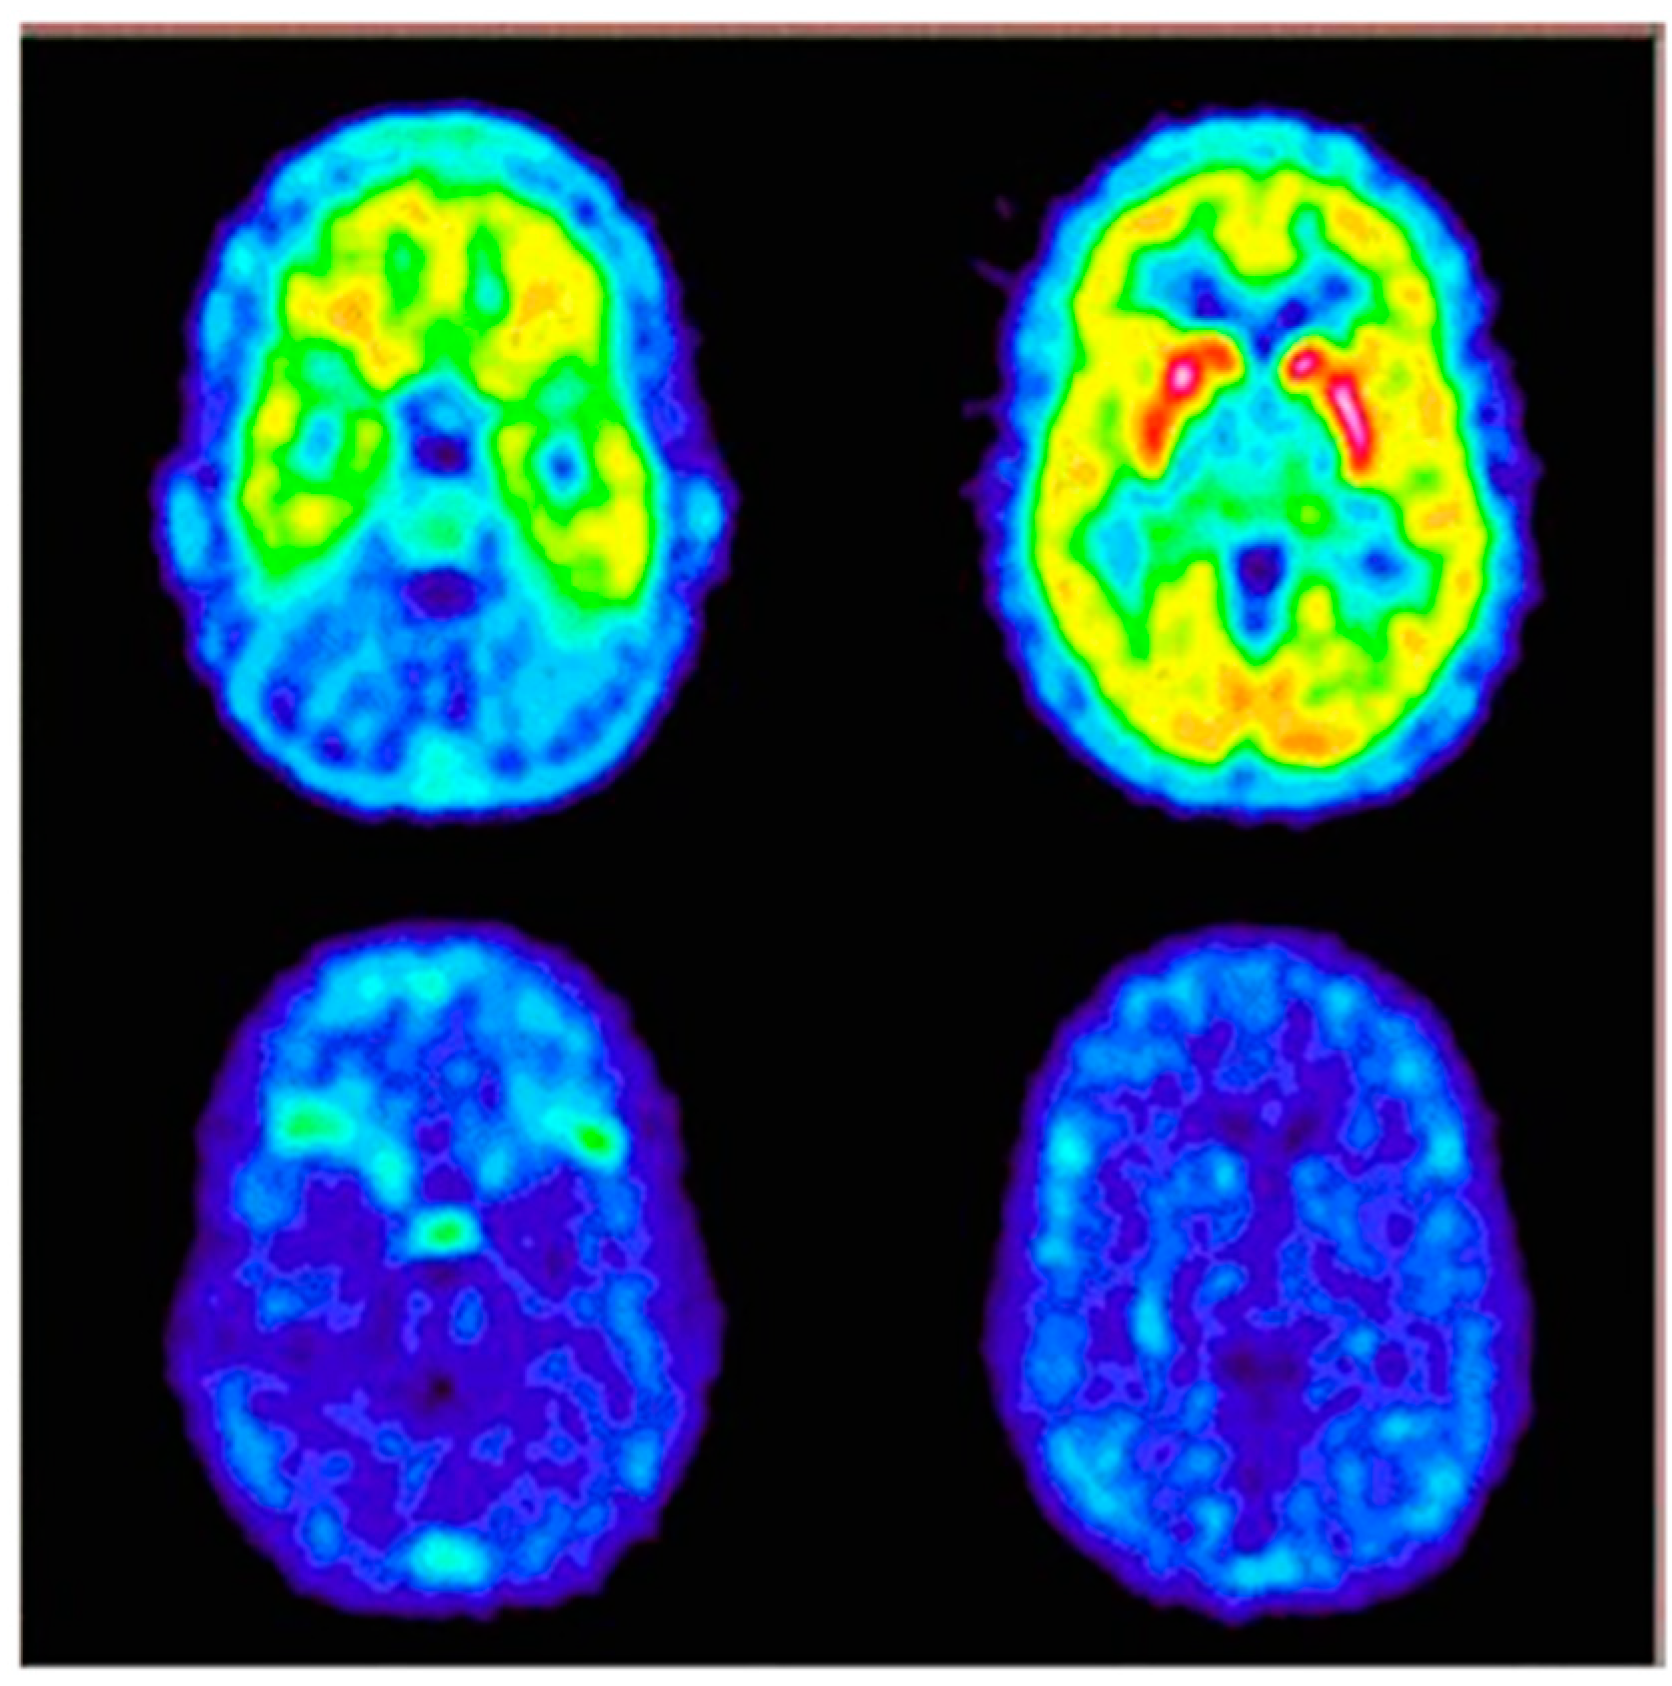

Meanwhile, it should also be noted that radiotracer molecular imaging is increasingly being used to determine receptor pharmacodynamics and optimize applicable effective doses of novel NK1R antagonists. One of the first clinical trials focused on this inspected a highly selective antagonist, aprepitant, while it was undergoing market authorisation. Determination of relationship between brain NK1R occupancy levels and aprepitant oral dose or plasma concentration was explored using [18F]SPA-RQ in single-blind, randomised, placebo-controlled studies in healthy participants [163]. Indeed, reliable cerebral NK1R occupancy prediction, according to aprepitant plasma concentration was determined. More than 90% of striatal receptor occupancy was reached in subjects with aprepitant plasma concentration around 100 ng/mL, after >100 mg/day of aprepitant for 2 weeks. Even though the study was conducted with a limited number of subjects and small variety of doses, it provided valuable indications for dosage regimens by which to achieve effective receptor blockage in the CNS (Figure 8).

Figure 8.

Predose (upper) and 100 mg aprepitant postdose (bottom) PET scans in the transverse section at the level of cerebellum (left) and striatum (right) in a human subject. Warmer colours symbolise higher uptake of radiotracer [18F]SPA-RQ. Based on ratio method with cerebellum reference, estimated receptor occupancy by aprepitant for this subject was 94% at 1053 ng/mL of aprepitant in plasma [163].